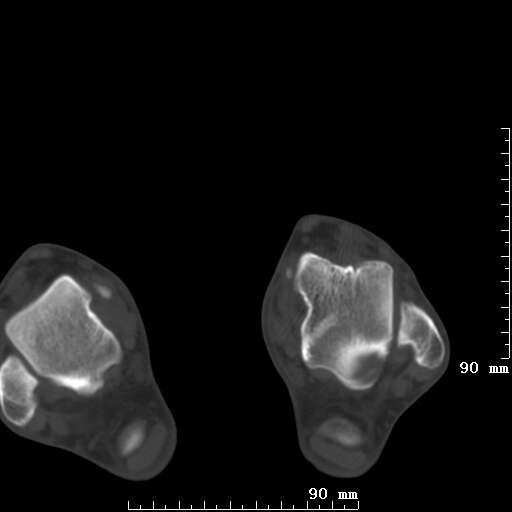

标题: CT19820:外伤一天,如何定性.男27Y [打印本页]

标题: CT19820:外伤一天,如何定性.男27Y

排除下创伤性关节炎吧,距骨有些囊变和硬化,周围韧带软组织有些机化、钙化。不是很像距骨无菌性坏死,感觉在关节面上的多,而不是距骨里面。

未见骨折及脱位像。距骨像是剥脱性软骨炎

支持!(踝关节距骨表面囊变和硬化 缺损)

距骨剥脱性软骨炎可能;踝关节创伤性关节炎?

未见明确新鲜骨折改变,距骨剥脱性软骨炎或踝关节创伤性关节炎可能。

关节周围多发高密度影,要结合病史